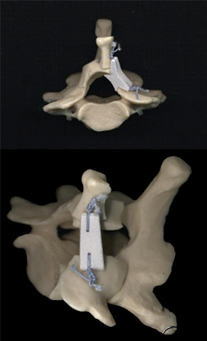

K-Spacer (有茎棘突起再生スペーサ) |

…棘突起固定用ツバにより脊柱管への落ち込みはありません |

…棘突起を正中に保持し左右均等に脊柱管の拡大が得られます |

…アライメントの改善に有用です |